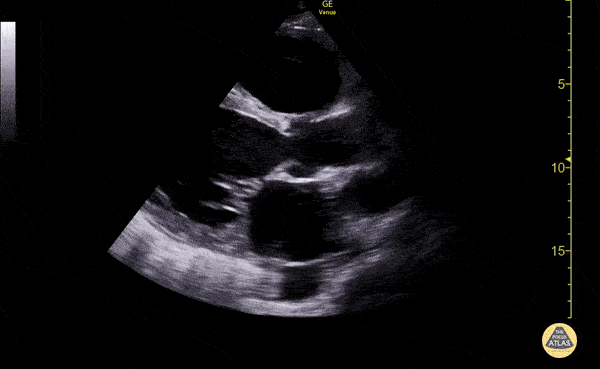

Left Ventricular Dysfunction - Reduced Ejection Fraction (Parasternal Long Axis View)

Patient with systolic heart failure with reduced ejection fraction. Nigist Taddese MBChB Division of Hospital Medicine, John H Stroger Hospital of Cook County